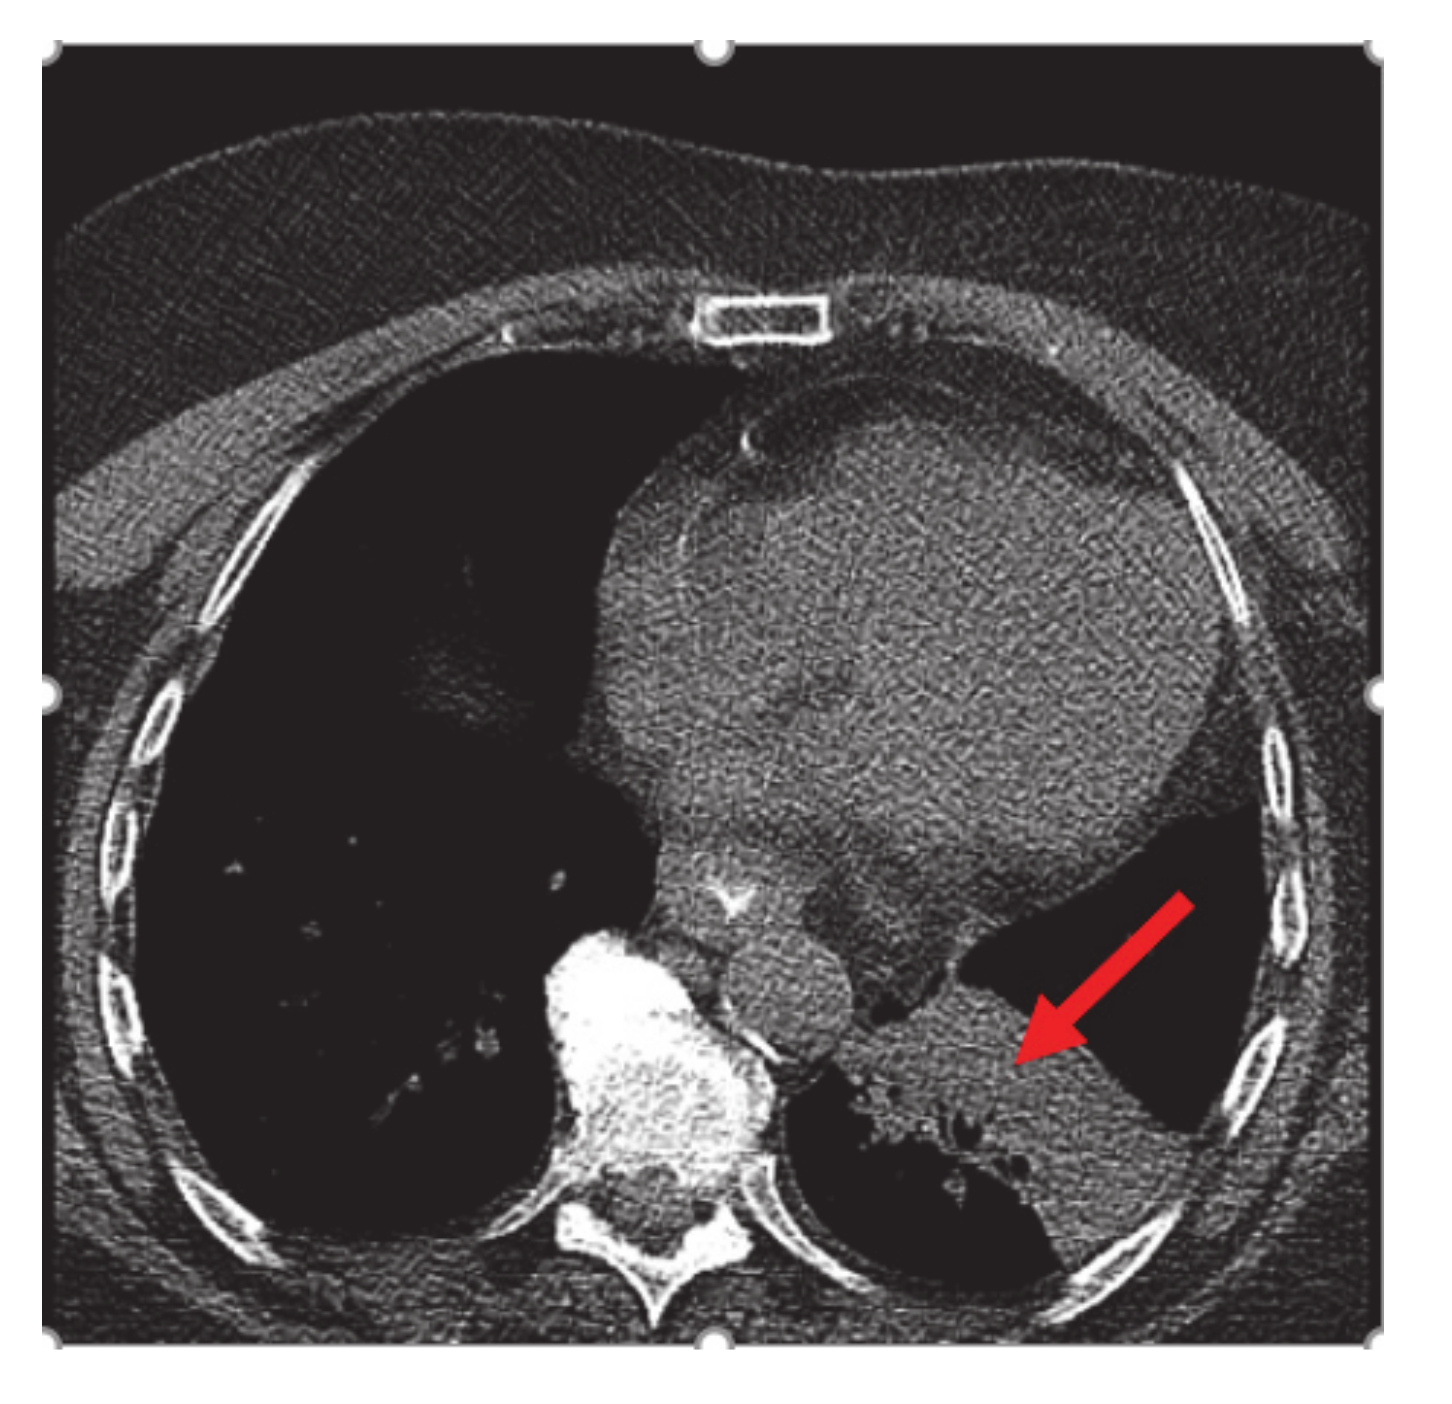

A 75-year-old non-smoker female with personal history of estrogen receptor (ER), progesterone receptor (PR) positive, Her2/neu negative breast cancer diagnosed 14 years ago, status post left breast lumpectomy, radiation, and 5 years of anastrozole with no evidence of recurrence, initially presented in early February 2020 for symptoms of persistent cough productive of green phlegm since January. She received azithromycin and prednisone for presumed pneumonia without improvement of symptoms. Later, she received levofloxacin and was referred to pulmonology for further evaluation. Computer tomography (CT) scan at that time showed left lower lobe consolidation/atelectasis with obscuration of proximal left lower lobe bronchus as well as mildly enlarged mediastinal nodes, concerning for underlying peribronchial lesion (Figure 1).

Figure 1.

CT chest: left lower lobe consolidation/atelectasis (red arrow) with obscuration of proximal left lower lobe bronchus and mildly enlarged mediastinal nodes.